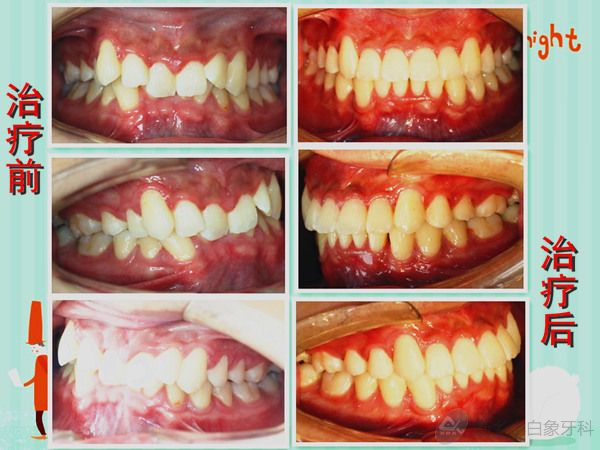

发布时间: 2014-06-27      患者李某某, 男,因“牙不齐、影响美观”来院治疗。初诊时间2011年7月4日,结束时间2014年5月1日。 接诊医生:李呈遥 患者非常满意,现将病例做一回顾性展示:

患者李某某, 男,因“牙不齐、影响美观”来院治疗。初诊时间2011年7月4日,结束时间2014年5月1日。

接诊医生:李呈遥

患者非常满意,现将病例做一回顾性展示: